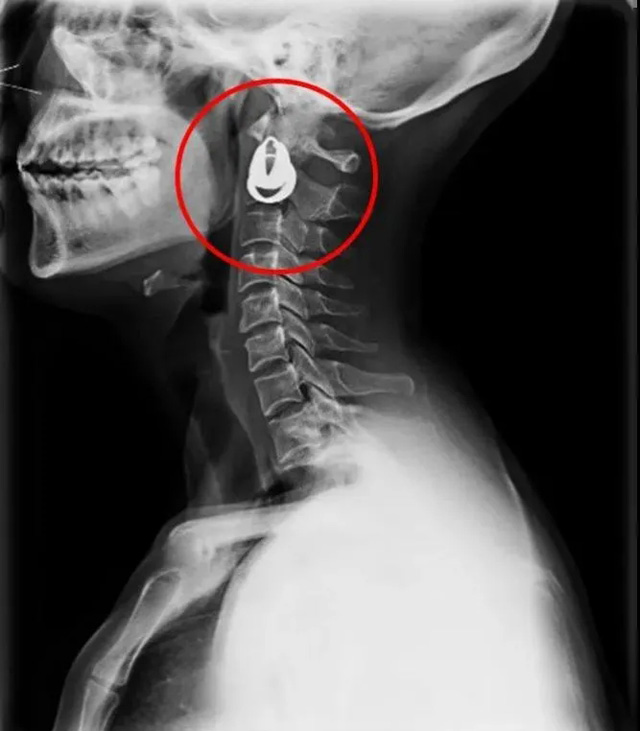

DR是一種比較常規(guī)的基礎(chǔ)影像學檢查方式,適用于人體各部位的健康普查及疾病檢查等優(yōu)勢,在臨床基礎(chǔ)檢查中備受醫(yī)生和患者的青睞。DR體檢車在健康體檢中有著非常重要的地位,由通過電纜串接在一起的探測板、掃描控制器、系統(tǒng)控制及影像顯示器等構(gòu)成。對比CT檢查而言,DR檢查的價格更低,輻射劑量更小它可以讓疾病預防,微細病變可更好顯示診斷治療提供科學的結(jié)果依據(jù)。很多外傷患者都要做DR檢查,來判斷是否骨折或其他的情況。體檢過程中面對DR體檢車做檢查時候需要準備注意什么呢?很多時候大家都有這樣的疑問,身上攜帶的物品是否會對圖像造成遮擋或給機器帶來干擾?檢查前如何準備才不會影響檢查準確性?